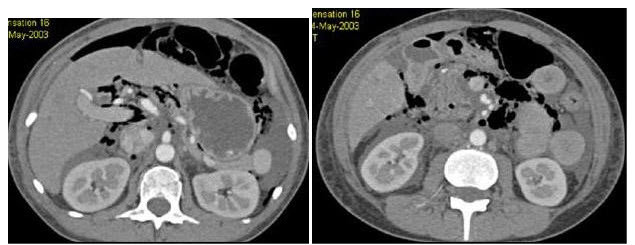

男,54岁,有乙肝病史,现腹胀,右上腹痛,消化不良,消瘦、乏力、贫血、黄疸,血清转氨酶升高,白蛋白/球蛋白比值倒置,CT、MRI检查如图,最可能的诊断是()

A.肝脓肿

B.局灶性结节增生

C.原发性肝癌

D.肝转移癌

E.肝炎性假瘤